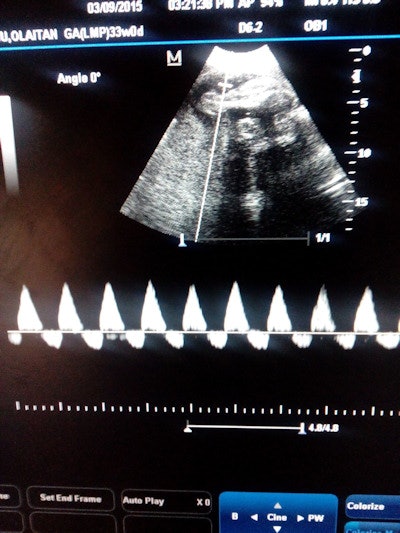

Ultrasound case sent via WhatsApp for remote expert consultation. All images courtesy of Dr. Victor Oboro from Ladoke Akintola University of Technology and Omvial 4D Ultrasound.What's more, patients appreciated the opportunity to have such easy access to remote expert consultations, according to lead investigator Dr. Victor Oboro of Ladoke Akintola University of Technology in Ogbomoso, Nigeria.

Ultrasound studies at the centers are acquired using a Voluson P6, P8, or i scanner (GE Healthcare), sometimes in multiple planes, Akinmoladun said. After an onsite ultrasound practitioner used a mobile device camera to take a picture of the ultrasound monitor, the image was sent -- along with textual information such as indications for the scan and any other relevant patient information -- via WhatsApp to five consultants at three university teaching hospitals in Nigeria for remote diagnosis.

In another case that sadly ended in tragedy, a sonographer performing a fetal heart assessment believed there was something unusual about the heart and sent the image as a video clip (see below) via WhatsApp for remote analysis.

Click image to view video. |